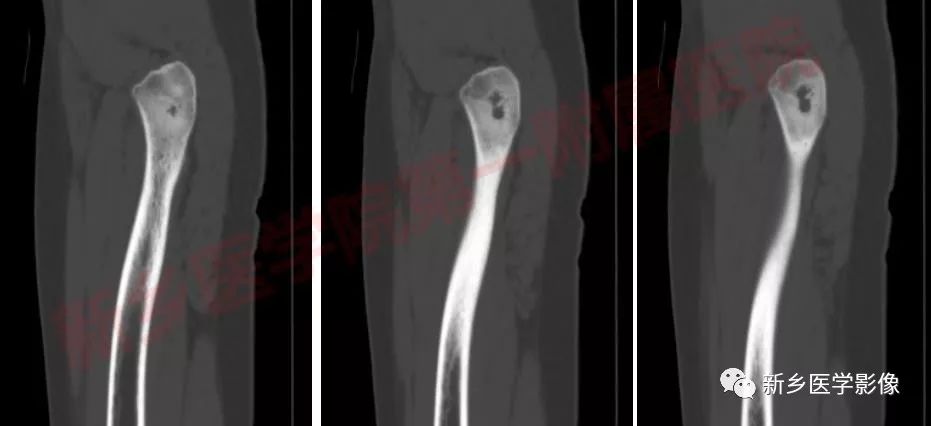

麻醉成功后,患者取仰卧位。常规消毒、铺巾,左臀部适当垫高。C臂透视定位后,沿左股骨大转子外侧,依次切开皮肤、皮下及阔筋膜张肌,暴露大转子,凿除少量骨质后,见一5*5*8mm骨质缺损,腔内见少量坏死样物质,周围骨质硬化。磨钻磨除空腔壁及周围硬化骨,蒸馏水浸泡后,生理盐水彻底冲洗伤口,手术室护士清点器械及敷料无误后,逐层关闭切口。

影像表现:

骨样骨瘤的影像学表现具有特征性,其典型的表现为:

瘤巢所在部位的骨质破坏及周围不同程度的骨质硬化,还可伴有骨膜反应、周围软组织或相邻关节的肿胀。

其中皮质型占70%,最常见,多见于长骨骨干。瘤巢靠近骨皮质内面,有小的透射线区域,周围是致密骨,若位于皮质内,则硬化环更明显。反应性增生硬化明显时,可遮盖瘤巢。

CT/平片上,“瘤巢”周围多出现反应性骨质增生硬化:松质骨增生硬化或骨膜反应